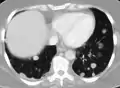

Pulmonary metastases shown on Chest X-Ray

The cells in a metastatic tumor resemble those in the primary tumor. Once the cancerous tissue is examined under a microscope to determine the cell type, a doctor can usually tell whether that type of cell is normally found in the part of the body from which the tissue sample was taken.

For instance, breast cancer cells look the same whether they are found in the breast or have spread to another part of the body. So, if a tissue sample taken from a tumor in the lung contains cells that look like breast cells, the doctor determines that the lung tumor is a secondary tumor. Still, the determination of the primary tumor can often be very difficult, and the pathologist may have to use several adjuvant techniques, such as immunohistochemistry, FISH (fluorescent in situ hybridization), and others. Despite the use of techniques, in some cases the primary tumor remains unidentified.